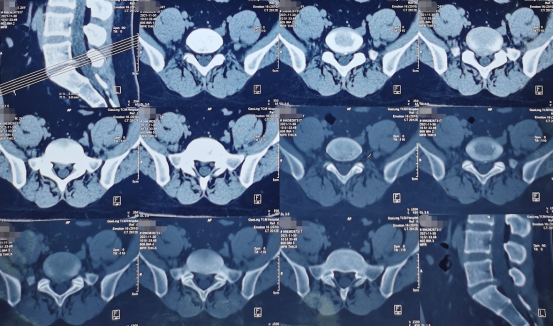

术前影像学资料

来到陕西冶金医院神经脊柱科后,由张少华主任、熊东主任接诊,经过各项检查后发现他在腰3/4、腰4/5、腰5/骶1都有不同程度的突出,尤其是在腰4/5突出非常严重。鉴于曹先生主要的症状表现和影像学等检查结合,判断腰4/5为主要责任节段,并建议尽快进行微创手术,给神经进行解压。